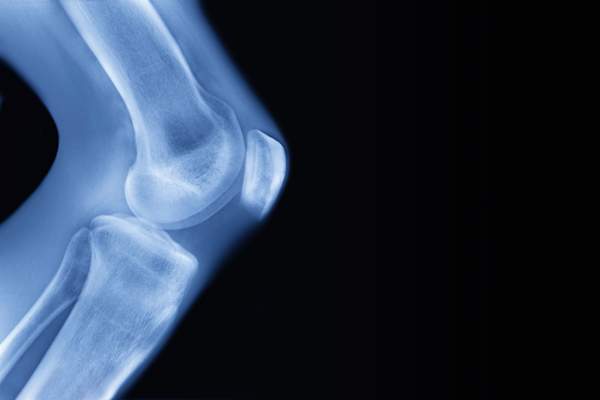

x光有助于诊断OA

金姆医生说,你的病史、体检和x光片将有助于诊断OA。在检查过程中,医生会观察你的关节并移动它们,以测试什么运动产生疼痛。(金姆博士说,如果挤压关节的运动导致疼痛,就有可能患上骨性关节炎。)x射线图像可以揭示骨头之间的空间是否变窄——这是软骨丢失的迹象。磁共振成像通常不需要,但可以提供更详细的肌腱和周围组织的图像——如果你的医生想要寻找退化的早期迹象,这很有用,金姆博士说。